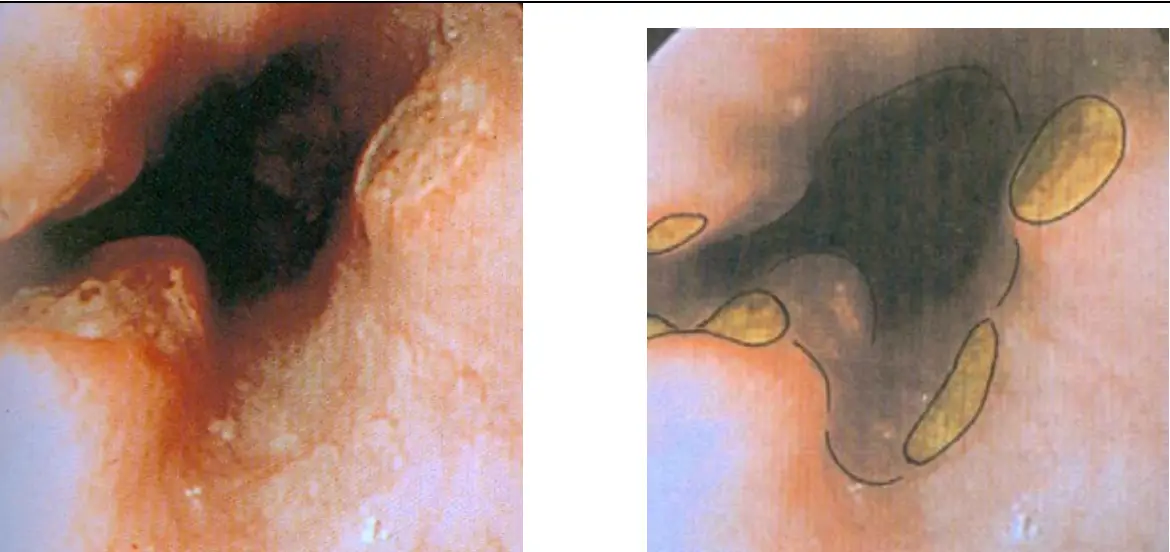

影像為兩張並列的食道內視鏡照片,呈現典型的藥物性食道炎表現:

左圖:食道管腔可見一個大型深色(黑色至深棕色)潰瘍病灶,潰瘍邊緣不規則,周圍黏膜充血水腫,表面附著白色纖維素性滲出物(fibrinous exudate)。潰瘍底部顯示組織壞死,此種「接觸性化學灼傷」外觀為藥片直接接觸食道黏膜所致。

右圖:同一或相近部位的標注圖,以黃色橢圓形標注出**藥片殘留物(pill fragments)**散落於潰瘍周圍,清楚呈現藥片滯留(pill lodgment)在食道黏膜上的狀態——這正是藥物性食道炎的直接致病機制(藥片未能順利通過食道,長時間接觸黏膜造成化學損傷)。

影像所見之位置與病灶特徵,符合食道中段(主動脈弓壓迫狹窄處)的藥物性潰瘍,而非食道下端,此點與本題正確答案直接相關。